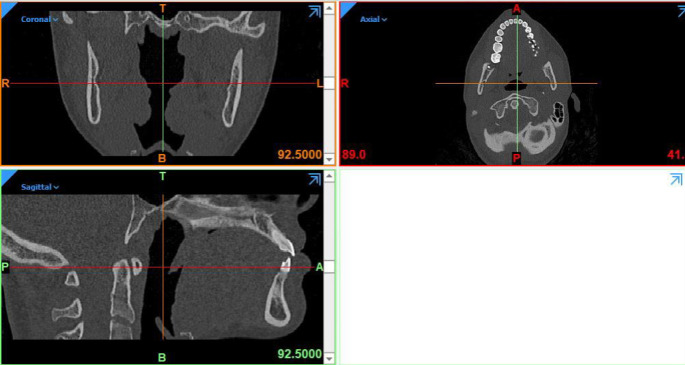

Methods: A 3-dimensional model of asymmetric mandible was obtained. SSRO with modified osteotomy was simulated unilaterally and another side osteotomized as common. Then differential set back was done and rigid fixation of that modified side with miniplate and monocortical screws was simulated then rigid fixation of other side by different fixation technics include 2 or 3 bicortical screws. With the force of 132N and 300N on the occlusal surface of first molars, the Von Mises Stress (VMS) distribution was calculated.